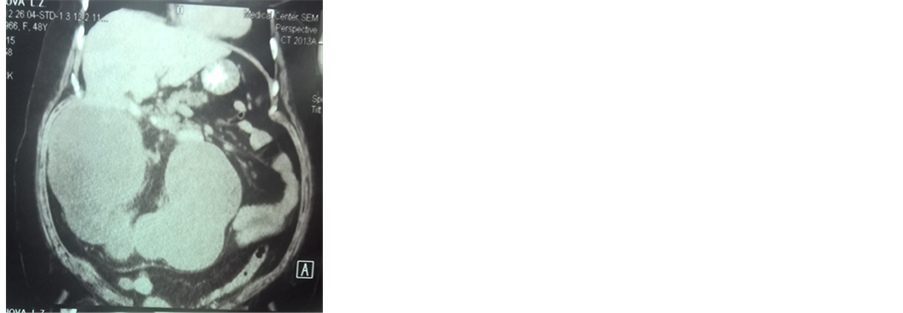

A 49-year-old female patient presented with right flank pain, nausea, vomiting, fever, general weakness for 2 weeks and developed abdominal distention of 10 days ago. Clinical evaluation of other systems did not reveal any abnormality. Endocrinologist consultation firstly found diabetes mellitus type 2. An abdominal ultrasound revealed a large abdominal mass. Whole abdomen CT found an abnormal right kidney, 234 × 300 × 279 cm in size, with tuberous distinct contours. In the projection of the pyelocaliceal system, CT revealed three stones up to 20 mm. The left kidney was normal 69 × 94 × 130 mm in size, parenchyma up to 27 mm, his Pyelocaliceal system was not expanded (Figure 1).

The patient underwent radical nephrectomy with a diagnosis of nonfunctioning left kidney due to giant pyonephrosis caused by stones (Figure 1).

Figure 1. Abnormal right kidney, with tuberous distinct contours and stones (arrow).